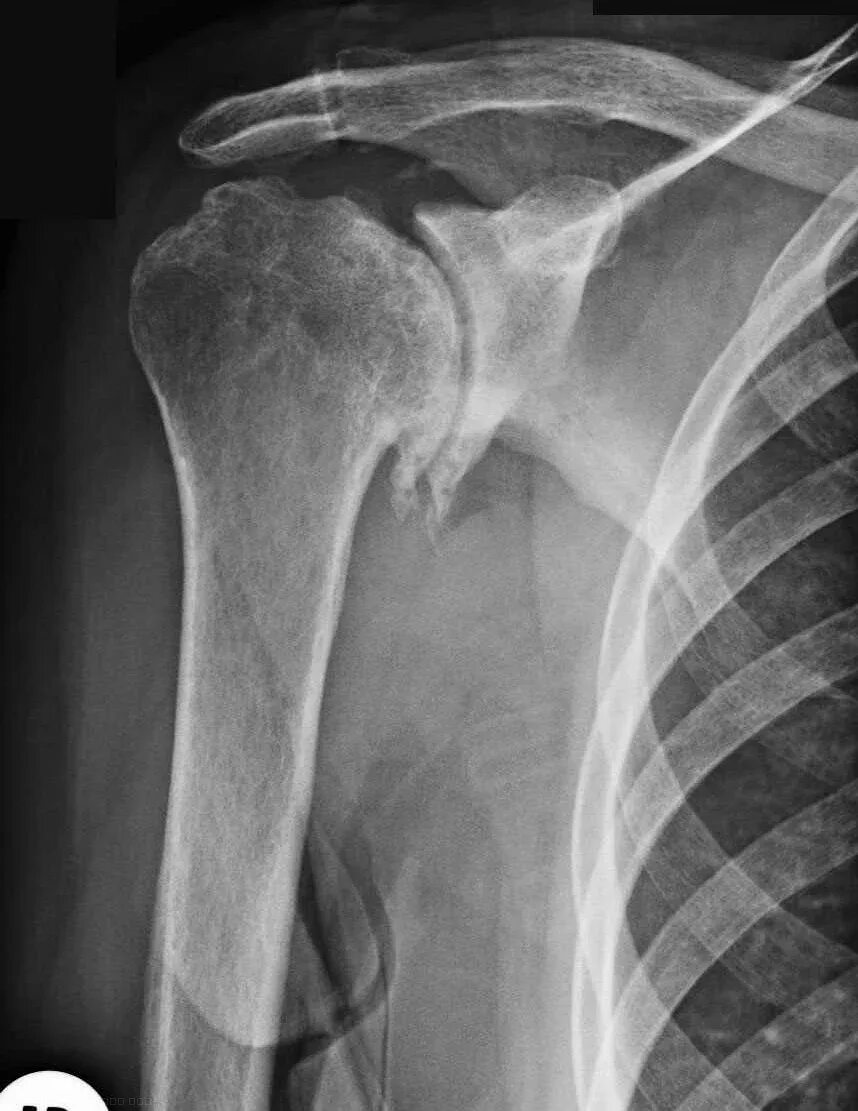

Как лечить сустав плеча